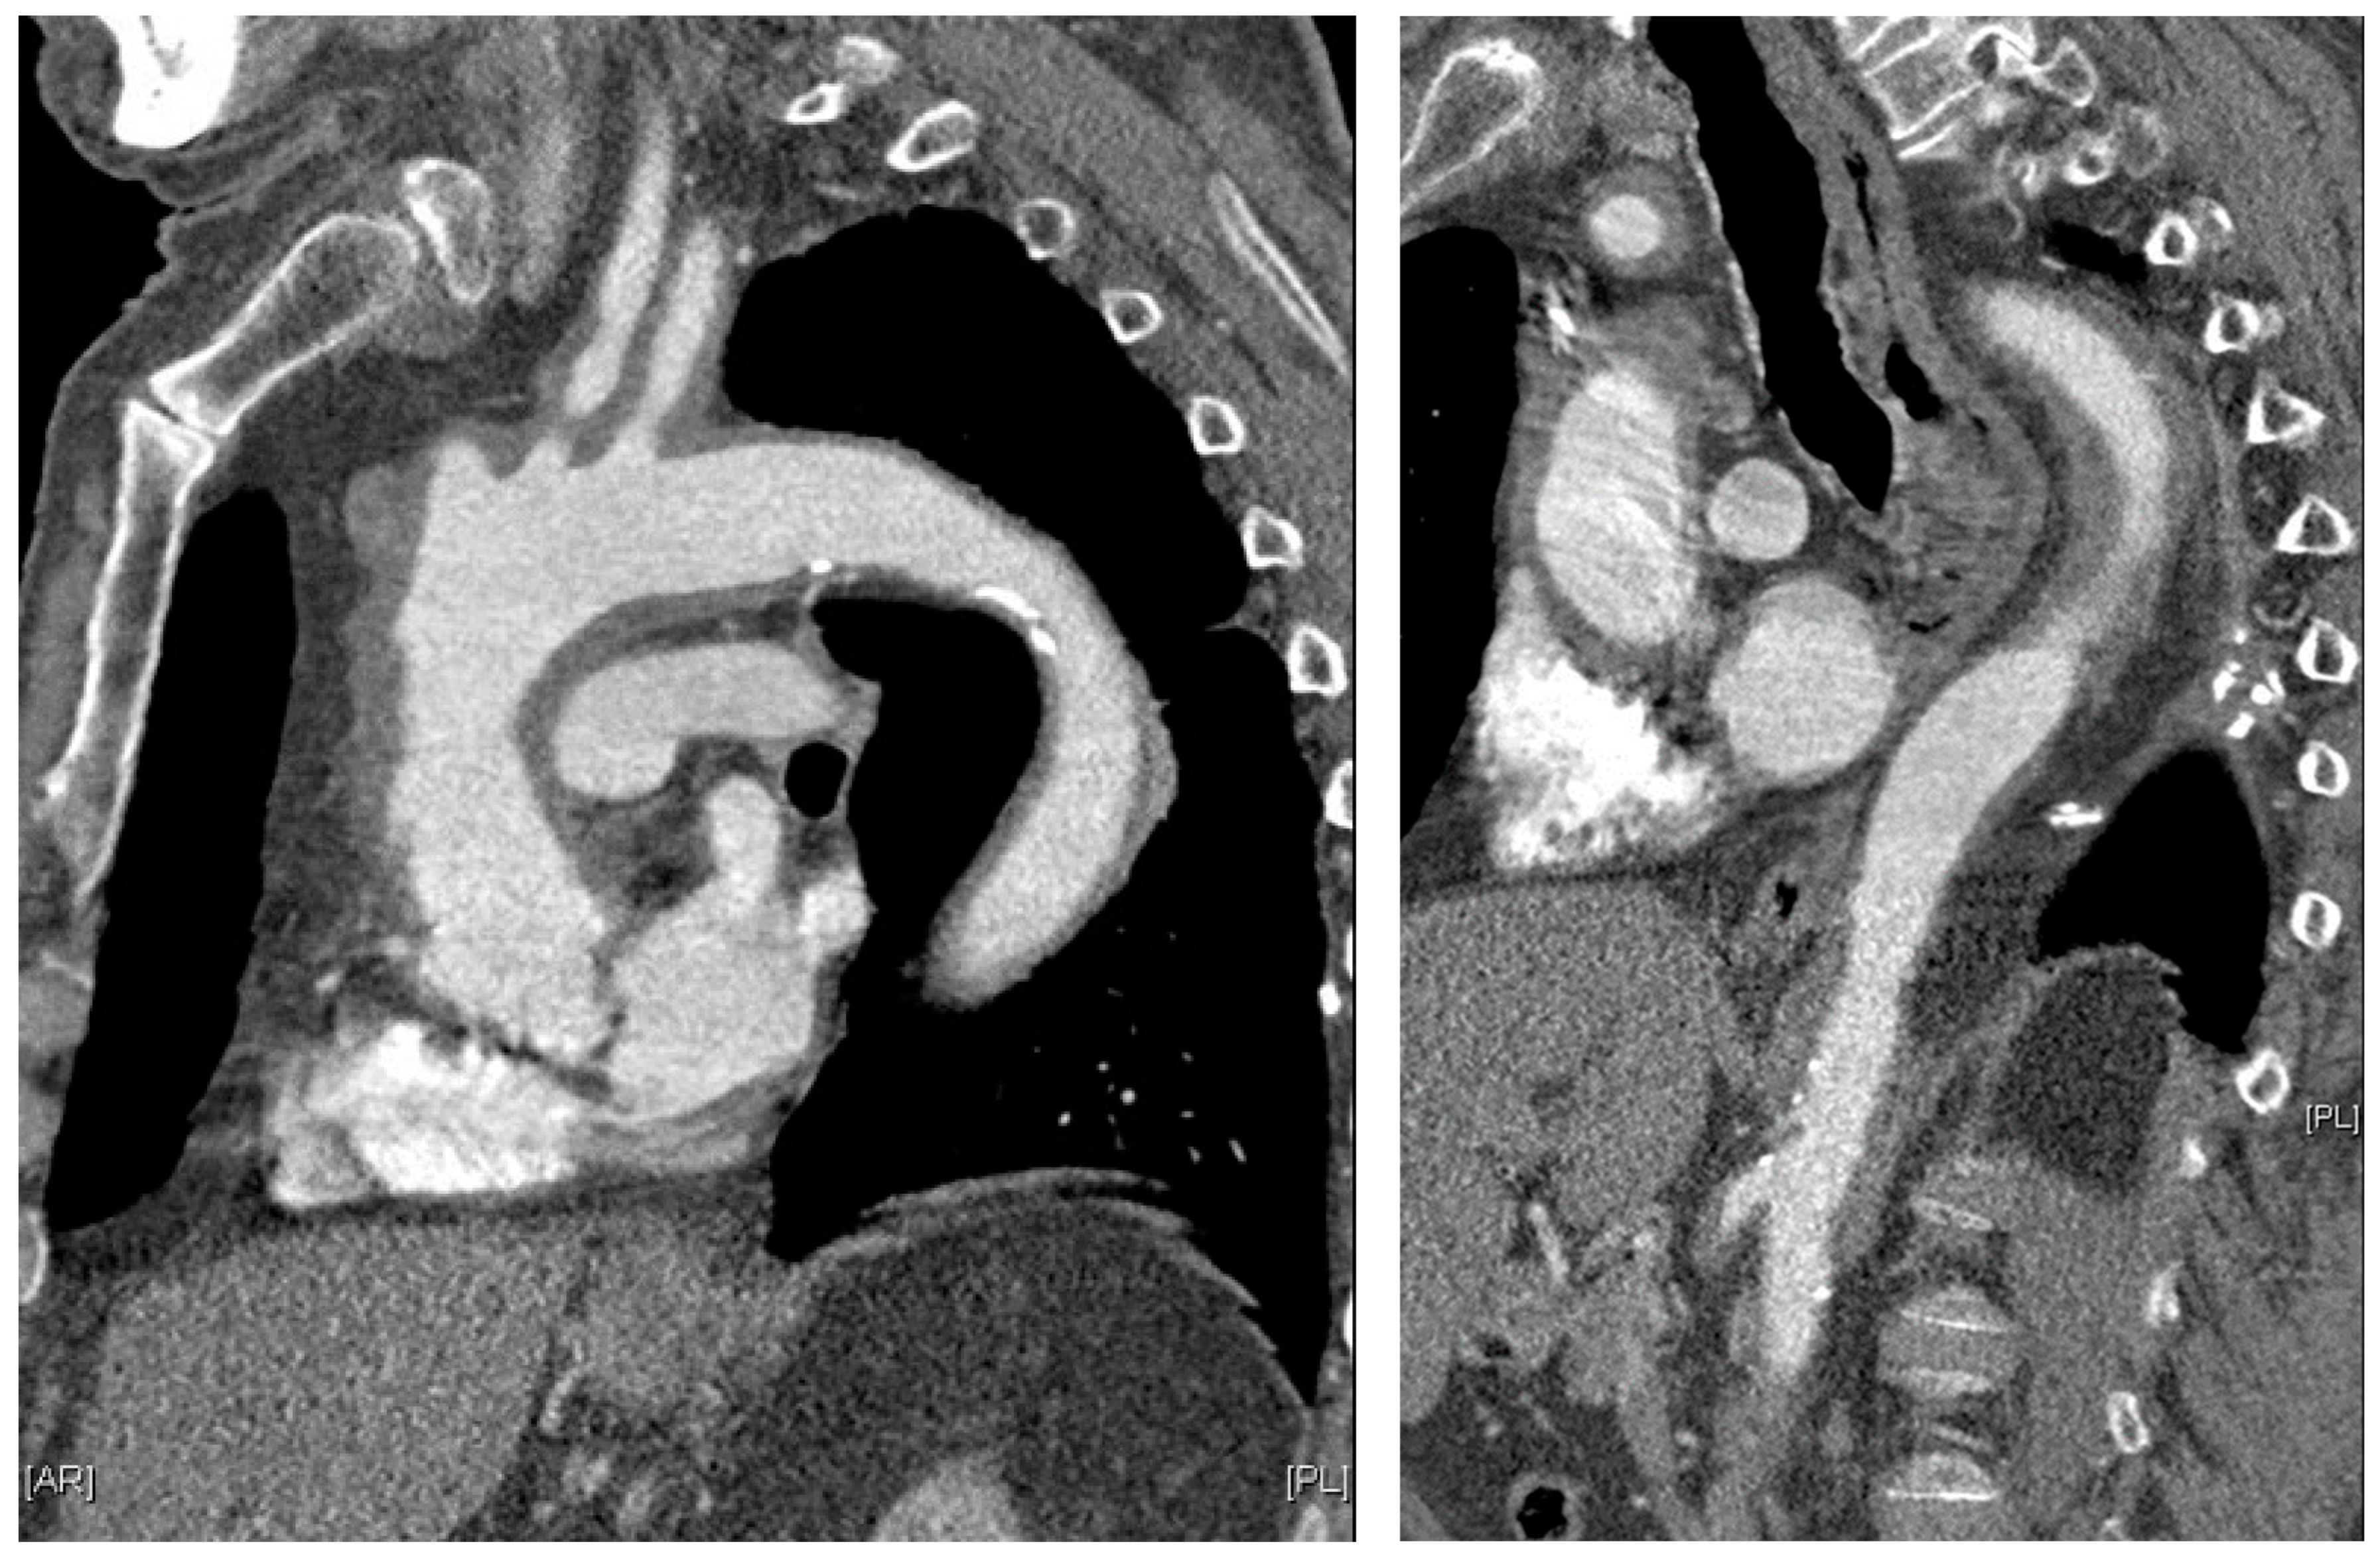

Figure 3. Parasagittal thoracic and sagittal abdominal MPR images on contrast-enhanced computed tomography: pronounced, circular, long-stretch vessel wall thickening of the aorta and its branches in giant cell arteritis. Courtesy of Dr. Corinna Schorn, Rheumatology Center, Rhineland-Palatinate.

Giant cell arteritis (GCA) affects typically large- and medium-sized arteries, including the carotid arteries and their extracranial branches, as well as the aorta and its branches [48]. Symptoms of GCA include headache, jaw claudication, tenderness of the temporal artery, and low-grade fever [49]. Typical complications of GCA include acute loss of vision and aortic aneurysms, which in turn can lead to more severe complications like stroke or aortic dissection [49,50]. GCA is frequently linked with polymyalgia rheumatica (PMR), characterized by muscle pain and bilateral morning stiffness in the proximal extremities. At a microscopic level, giant cells infiltrate the vascular wall, leading to an occlusion of the affected blood vessels and thus to ischemia of the tissue to be supplied [51]. The diagnosis of PMR/GCA is usually based on clinical presentation, imaging, temporal artery biopsy (Figure 2C,D, Figure 3 and Figure 4), and the ACR/EULAR classification criteria [49,52].